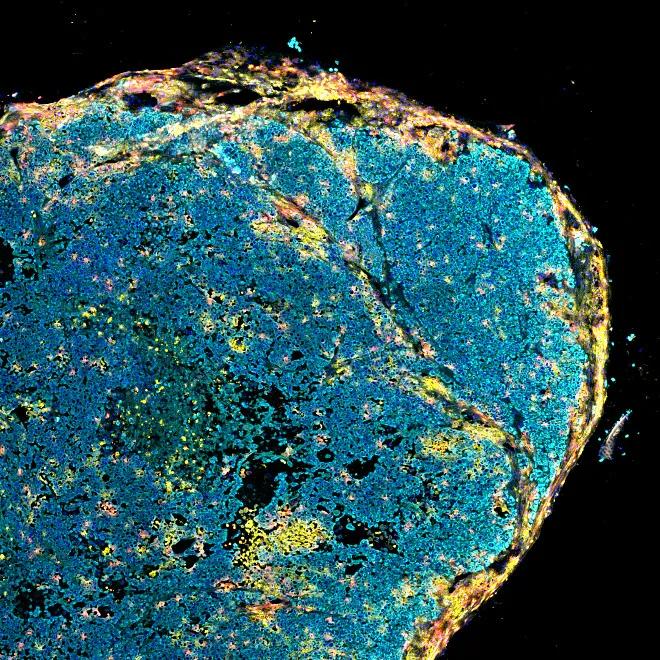

Cancer Model Characterization which includes: